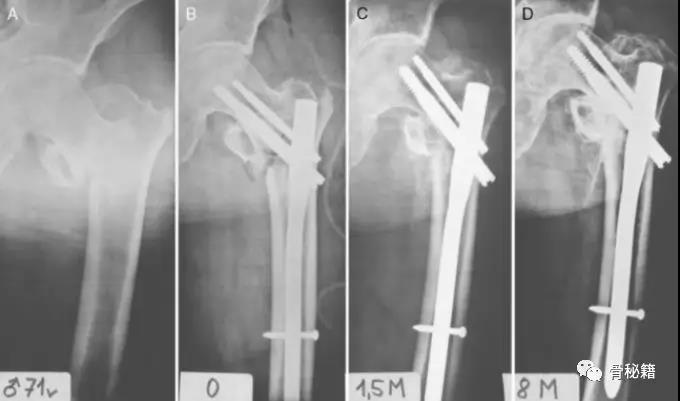

断端断裂通常是疲劳断裂,也有部分外伤导致的断裂。疲劳断裂通常在好几个月到几年的时间不等。骨折长期不愈合所导致

骨折复位不良、断端无接触、没有动力化、粗隆下骨折应力较大。骨折延迟愈合,6个月的时候发生了断钉

7个月 骨折延迟愈合断钉